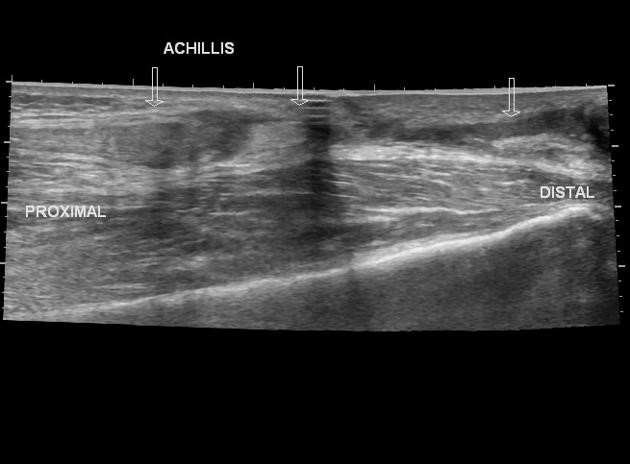

Ultrasound can be used to diagnose a variety of MSK injuries and disorders.

Focused ultrasound imaging has proven to be a useful and cost-efficient tool to many providers when diagnosing and treating their patients. MSK imaging is

primarily used to evaluate traumatic, inflammatory, and degenerative conditions of structures. When superficial imaging is required, ultrasound can

achieve extremely high resolution, quite comparable to that of MRI or CT scanning. It identifies damage or problems in joints, tendons, ligaments, muscles

and nerves where the patient has pain. The ability to provide a dynamic component while evaluating MSK structures gives light to injuries that could otherwise

not be seen.

• Tendinosis/Tendinitis

• Tendon and ligament tears